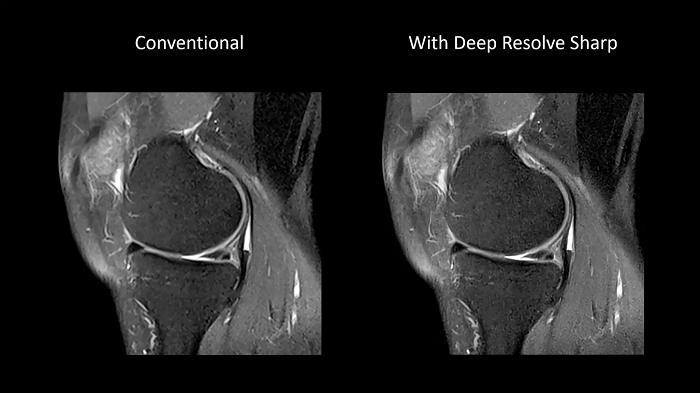

Deep Resolve Sharp

Using a convolutional neural network of TSE sequences, Deep Resolve Sharp produces high-resolution images from low-resolution input. Sharper and crisper images can be achieved without compromising on data acquisition time.

Image Courtesy: University Hospital Erlangen, Germany | Image-ID: 4aaaa0459